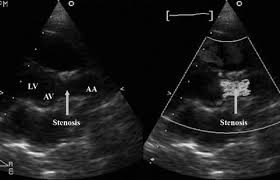

Supravalvular aortic stenosis williams syndrome. It can be a familial disorder can occur sporadically or associated with Williams syndrome WS which is a neurodevelopmental disorder affecting connective tissue and the central nervous system. Supravalvar aortic stenosis SVAS is a fixed form of congenital left ventricular outflow tract LVOT obstruction that occurs as a localized or diffuse narrowing of. The diagnosis can be made by echocardiography or MRI.

This form of cardiovascular disease is called supravalvular aortic stenosis SVAS and occurs frequently in people with Williams syndrome. A discrete subaortic stenosis was identified by echocardiography. Some individuals with SVAS have associated abnormalities such as peripheral pulmonary artery stenosis.

This form of cardiovascular disease is called supravalvular aortic stenosis SVAS and occurs frequently in people with Williams syndrome. This form of cardiovascular disease is called supravalvular aortic stenosis SVAS and occurs frequently in people with Williams syndrome. After that he was good for a long time says Karen. Patients with congenital supravalvular aortic stenosis and associated peripheral pulmonary artery stenoses the majority of whom have Williams-Beuren syndrome are inherently at risk for development of myocardial ischemia. Williams syndrome is a rare affecting 1 in 10000 people developmental disorder that can affect many parts of the body including the heart and blood vessels. The diagnosis can be made by echocardiography or MRI. Children with Williams syndrome have mild to moderate intellectual disability distinctive facial features and an outgoing personality.